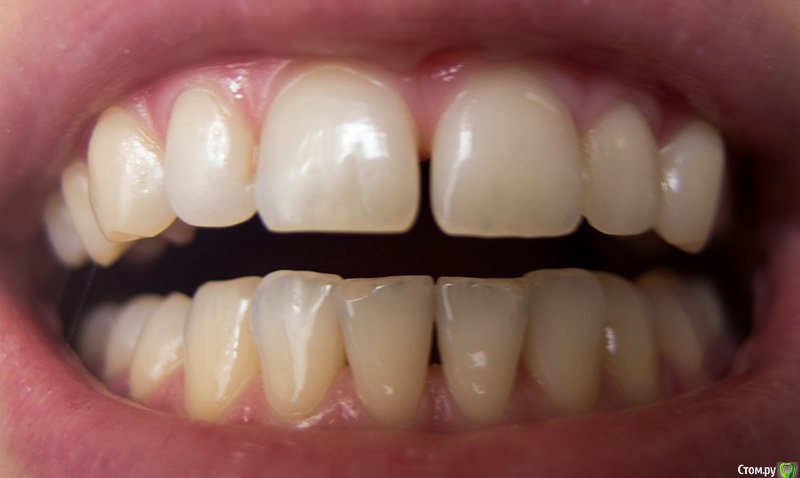

ptichka Опубликовано 1 марта, 2015 Поделиться Опубликовано 1 марта, 2015 ЗдравствуйтеМне 34 года.Беспокоит субъективно продолжающееся уменьшение межзубных сосочков между нижними резцами (впервые заметила около 10 лет назад) - особенно центральными, и по чуть-чуть между центральным и боковым резцом на обеих челюстях.Эта проблема почти не заметна в жизни, т.к. промежуток заполняется слюной и отсвечивает.Зубы не шатаются, зубного камня нет (то есть он не образуется). Имеет ли смысл делать рентген и т.п. Если межзубные промежутки действительно атрофируются, есть ли какое-то лечение в данный момент? Если какой-то способ сделать десневой сосочек более объемным в чисто косметических целях? Ссылка на комментарий

krokomot Опубликовано 2 марта, 2015 Поделиться Опубликовано 2 марта, 2015 Судя по снимку и фотографиям у вас все в порядке, разве что чистите неправильно зубы. Беспокоится особенно не о чем. 1 Ссылка на комментарий